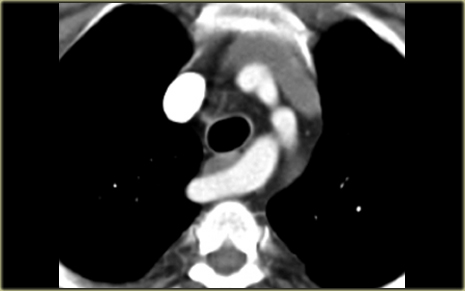

On the left a patient with a left superior intercostal vein.

Notice the ‘aortic nipple sign’.

On the left another example of a left superior intercostal vein.

It courses along the lateral margin of the aortic arch from the the accessory hemiazygos vein to the left brachiocephalic vein.